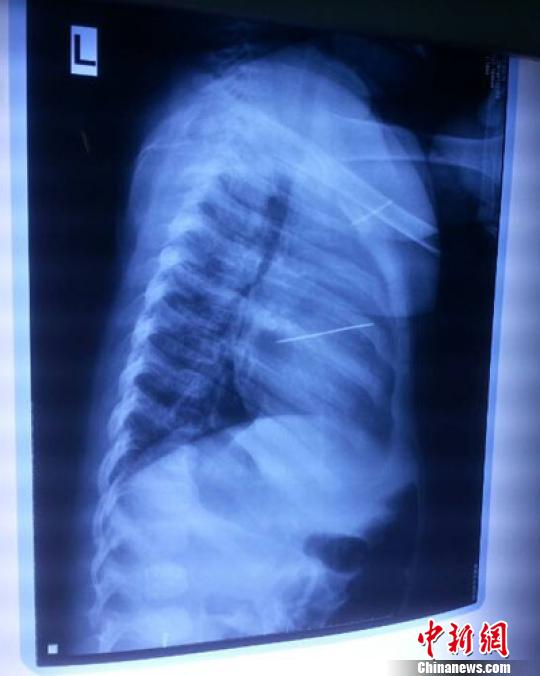

女?huà)胄仄崾拘呐K里面扎了一個(gè)縫衣針 蔡迅翔 攝

醫(yī)院胸心外科主任翟波介紹說(shuō),1月22日,小患者彤彤因?yàn)榘l(fā)燒抽搐來(lái)醫(yī)院就診,常規(guī)檢查時(shí)發(fā)現(xiàn)孩子心臟里面扎了一個(gè)縫衣針。

“第二天上午,我們做了個(gè)緊急彩超檢查,發(fā)現(xiàn)針是從患者右心室表面刺入,穿破室間隔,到達(dá)左心房,中間還有一部分損害到二尖瓣。于23號(hào)下午,我們就做了一個(gè)緊急手術(shù),手術(shù)中發(fā)現(xiàn),這枚針已經(jīng)刺入心臟,沒(méi)入了右心室的下面,表面已經(jīng)看不到針了,僅能看到一個(gè)小針眼,還在往外滲血,一點(diǎn)一點(diǎn)的滲,心包腔里面大概有100多毫升的出血,心包上一個(gè)洞,針在右心室表面刺入以后,穿過(guò)室間隔,在二尖瓣的上方,進(jìn)入了左心房,在針的四周,有很多纖維沉積物,包繞著這枚針?!钡圆ㄕf(shuō),他們把針取出來(lái)以后,測(cè)量了一下,長(zhǎng)度大概是五厘米,同時(shí)發(fā)現(xiàn)這個(gè)針給患者左心房的后壁造成了一定的損傷,左心房的后壁已經(jīng)損傷了三分之二,還剩下有左心房的外膜,很薄的一層,如果這一層再破的話,這個(gè)孩子將會(huì)引起大出血,很快就會(huì)死亡。